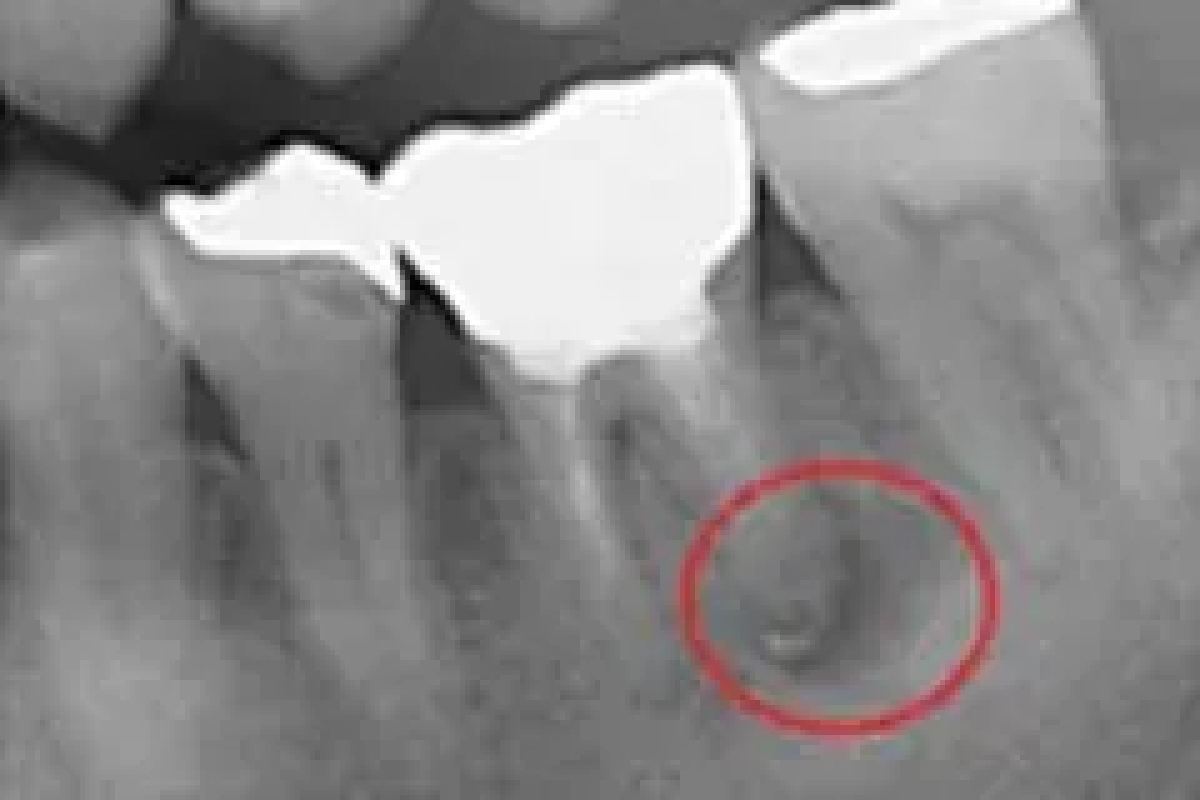

当院で処置した症例をご紹介します。

他院で抜歯と言われてしまった歯でも抜歯せずに対処した症例も多数あります。

黒い影が出ている部分が問題の個所で(根尖病巣)、治療後はこの影がなくなっているのが見て取れると思います。

Before

価格は約2万円。根管を治療した症例。リスクとして、低い可能性ではあるが、再発する可能性がある。